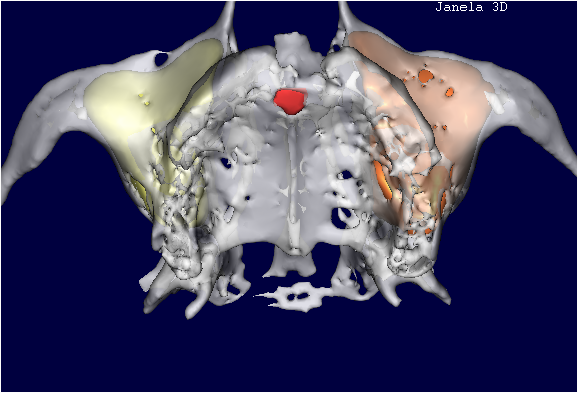

TOMOGRAFIA COMPUTADORIZADA APÓS A REALIZAÇÃO DO ENXERTO ÓSSEO DE BANCO DE OSSO